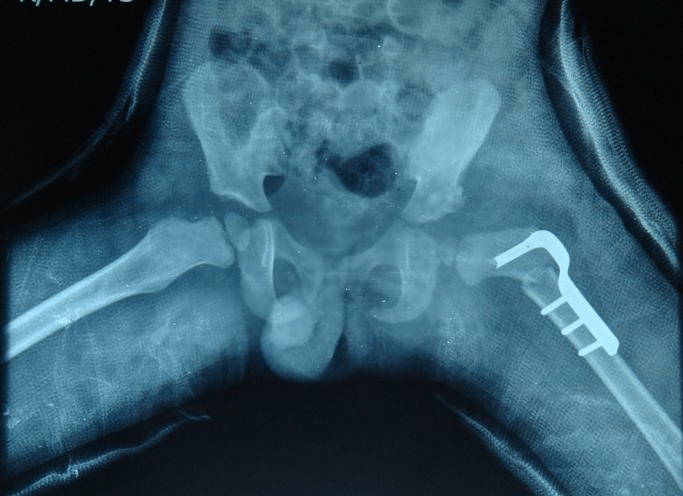

3+5 year old Pre and post-op (Adductor tenotomy hip, OR, Femoral & Pelvic Osteotomy with spica)